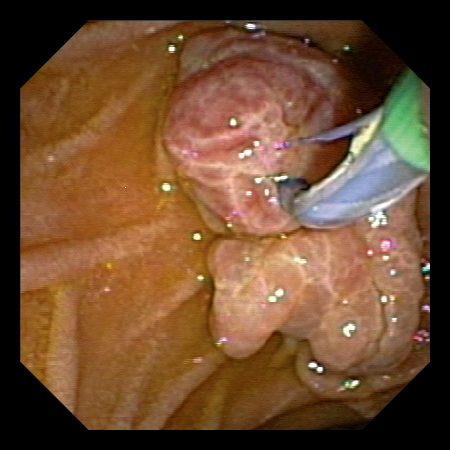

息肉切除

高功率切割

瞬間投入高輸出功率,從而在開始切割時發揮穩定切割的功能,有助於減輕開始切割時的卡頓等不適感。